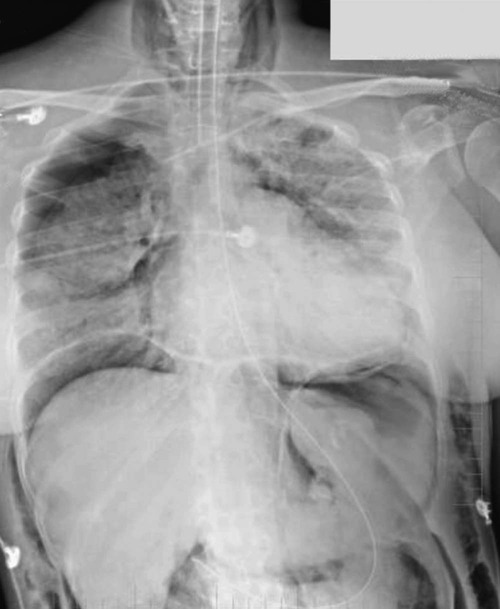

The first description of ARDS appeared in a remarkable case series reported in 1967.7 Ashbaugh and colleagues described 12 patients ranging in age from 11 to 48 years who presented with respiratory distress, hypoxemic respiratory failure, and patchy bilateral opacities on chest radiographs (Fig. 100-2). Most of the cases were preceded by severe trauma or viral infection and the onset of symptoms was relatively rapid, with most patients developing respiratory distress within 48 to72 hours of the beginning of their illness. Many patients required positive pressure ventilation and exhibited low respiratory system compliance, and some experienced improvement in oxygenation with the application of positive end-expiratory pressure (PEEP). This syndrome was initially termed the adult respiratory distress syndrome to distinguish it from the respiratory distress syndrome seen in infants. Subsequently, recognizing that the syndrome can also develop in children, it was renamed the acute respiratory distress syndrome.